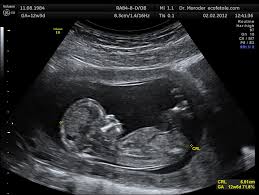

This picture depicts this amount of weeks into pregnancy during the placenta previa phase.

What is 18-22 weeks?

The primary tool used to diagnose placenta previa.

What is an ultrasound?